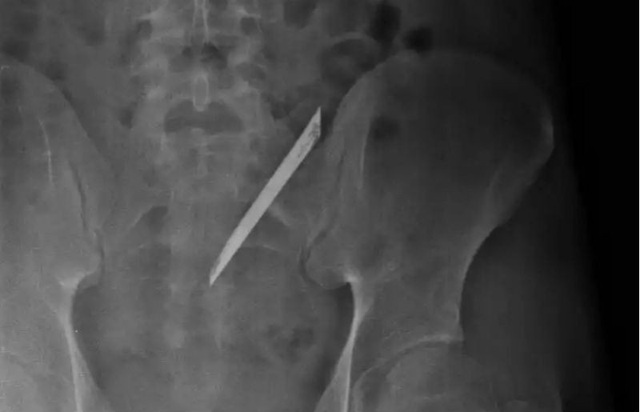

Ê-kíp bác sĩ khoa Ngoại tổng quát bệnh viện Nhân Dân 115 (TP.HCM) vừa phẫu thuật lấy lưỡi dao Thái Lan dài 12 cm nằm trong lưng 4 năm của anh Quang (tên bệnh nhân được thay đổi, 24 tuổi, ngụ quận 6).

Theo bác sĩ khoa ngoại tổng quát, đây là trường hợp hi hữu. Lưỡi dao dù đã nằm lâu năm trong cơ thể người bệnh nhưng không đâm vào cột sống, nên không ảnh hưởng đến thần kinh.